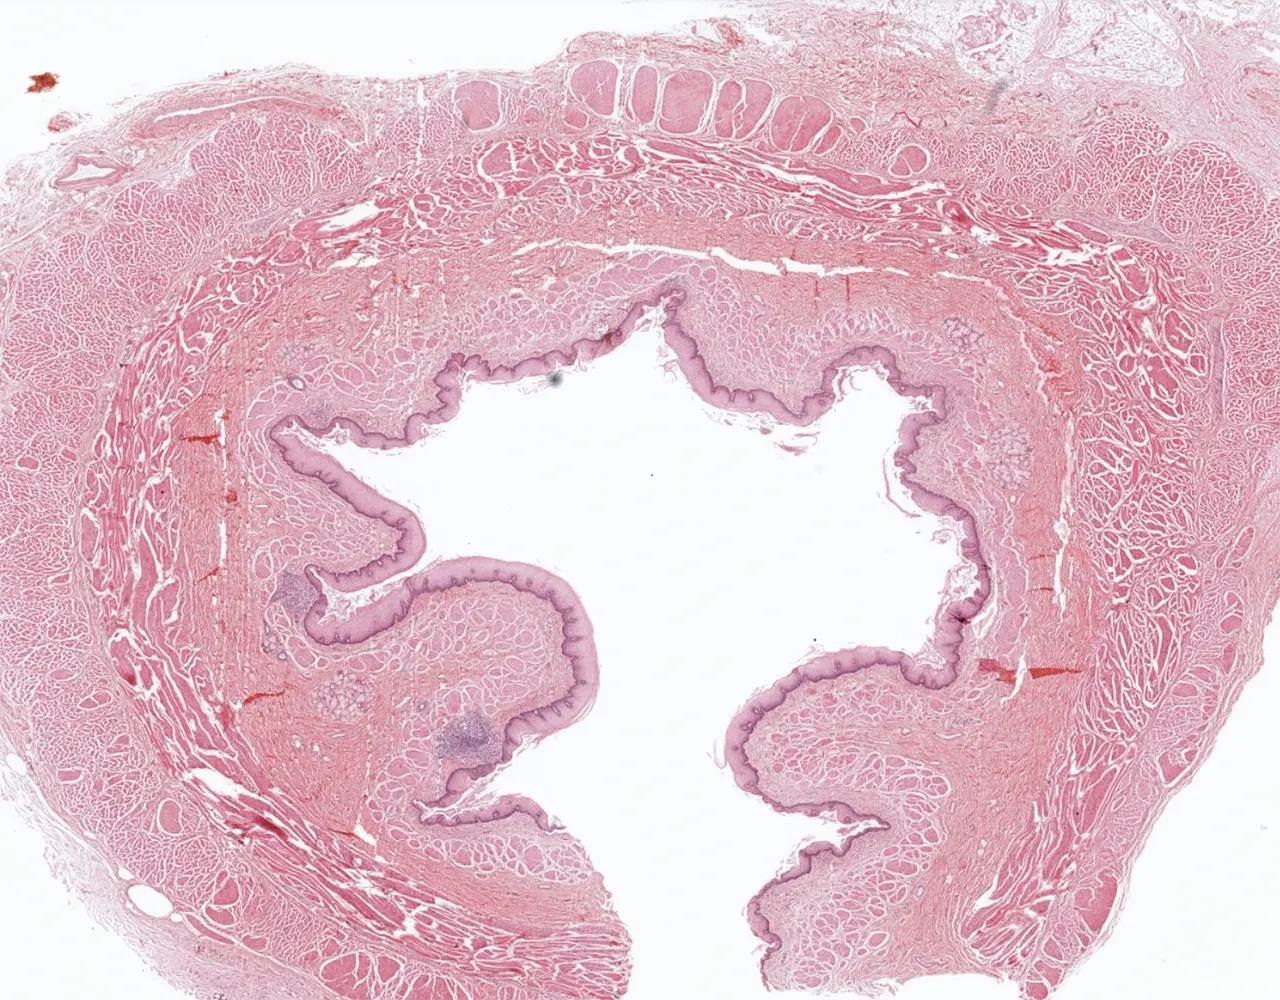

- Microscopically, the esophagus is composed of four layers: mucosa, submucosa, muscularis propria, and adventitia.